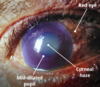

Examination

- Red eye

- Fixed dilated pupil

- Corneal haze

- Teary

- Decreased visual acuity

- Firm eye on palpation